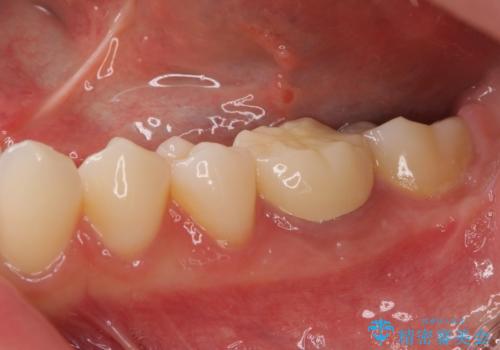

海外転勤が決まり、急いでセラミック治療をしてほしいとご来院された患者様です。

根管治療に症状がなく、上の歯に関しては土台もそのまま使用可能であったため、下の歯の土台、上下の歯のセラミック治療を行いました。